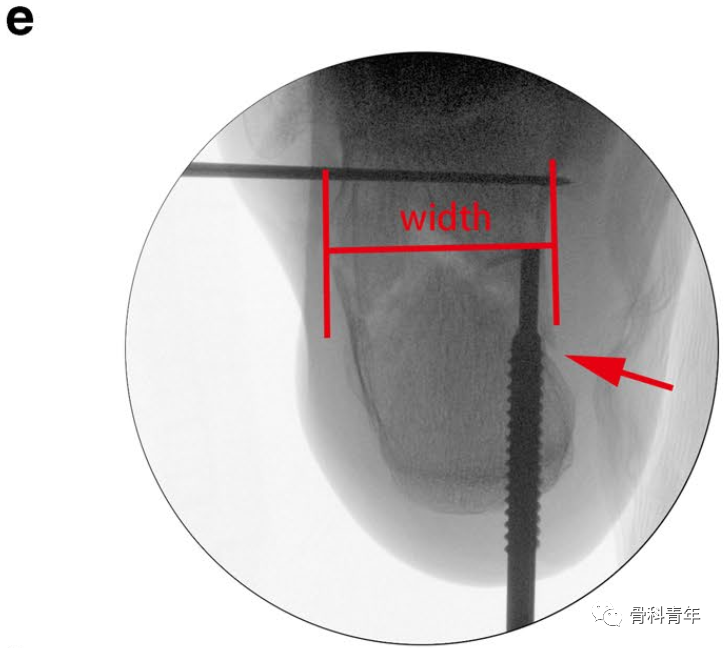

通过另一例跟骨后关节面压缩患者,可进一步理解该撑开器的复位作用:该患者后关节面压缩严重,跟骨高度丢失。

采用血管钳及克氏针撬拨,后关节面恢复有限,后关节面仍存在台阶(图中绿线所示)。

采用撑开器可实现后关节面的复位。